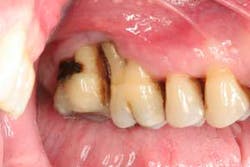

Figure 3: Initial presentation in 2011 of the mandibular anterior sextant, showing advanced hard- and soft-tissue loss.

At presentation, Martin was in his fifties with a medical history significant for controlled hypertension with no known food or drug allergies. He had been lackadaisical with his dental care in the past because of his busy schedule, but he was motivated to get his hygiene and treatment under control. He denied a history of smoking/alcohol/drug use. Based on his full-mouth series (figure 1) and clinical presentation, Martin had generalized, moderate bone loss with localized, severe bone loss in the posterior maxillary right and left quadrants (figures 2a and 2b) as well as the mandibular anterior incisor area (figure 3).